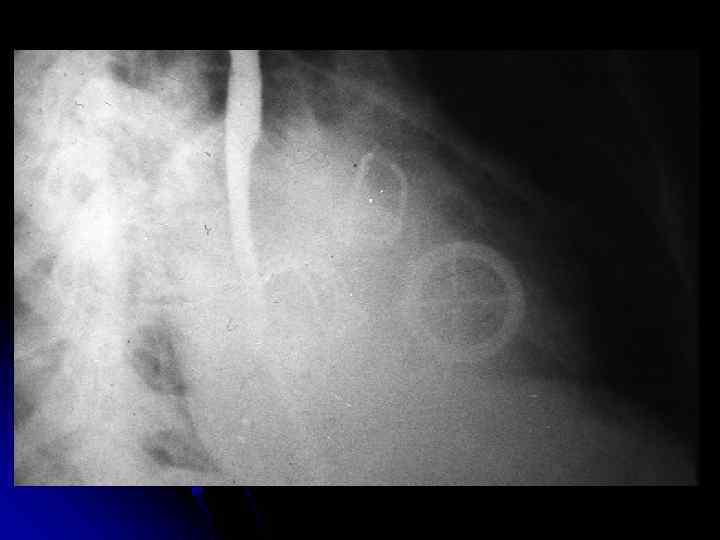

Рентгенограмма грудной клетки больного с недостаточностью трехстворчатого клапана во второй косой проекции.